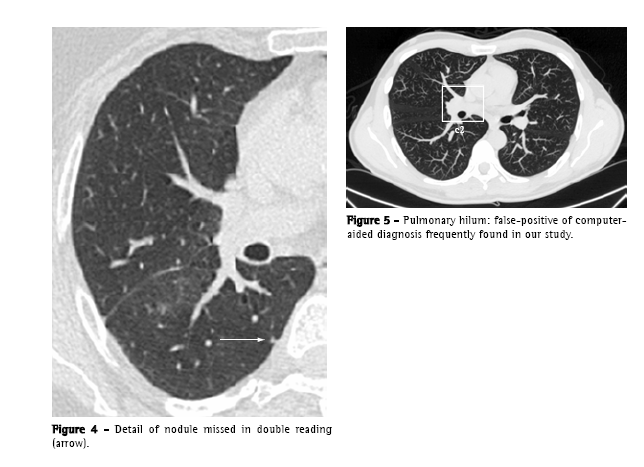

Only one true nodule (<1% of total true nodules), that was highlighted by the CAD, had not been registered by the image double reading process. It

was an ill-defined, 4-mm subpleural nodule, located in the right lower lobe (Figure 4).

The mean number of false-positives per test (10.9), despite being within the range found in other studies (3-13 false-positives per CT scan of the chest),(21) is considerable, constituting a tiresome and time-consuming factor in the review of the data provided by the computer. The false-positives found were, principally, vascular structures, and are in accordance with those reported in the literature, except for the hilar structures (Figure 5), which are not often specifically cited.(9,19,22)